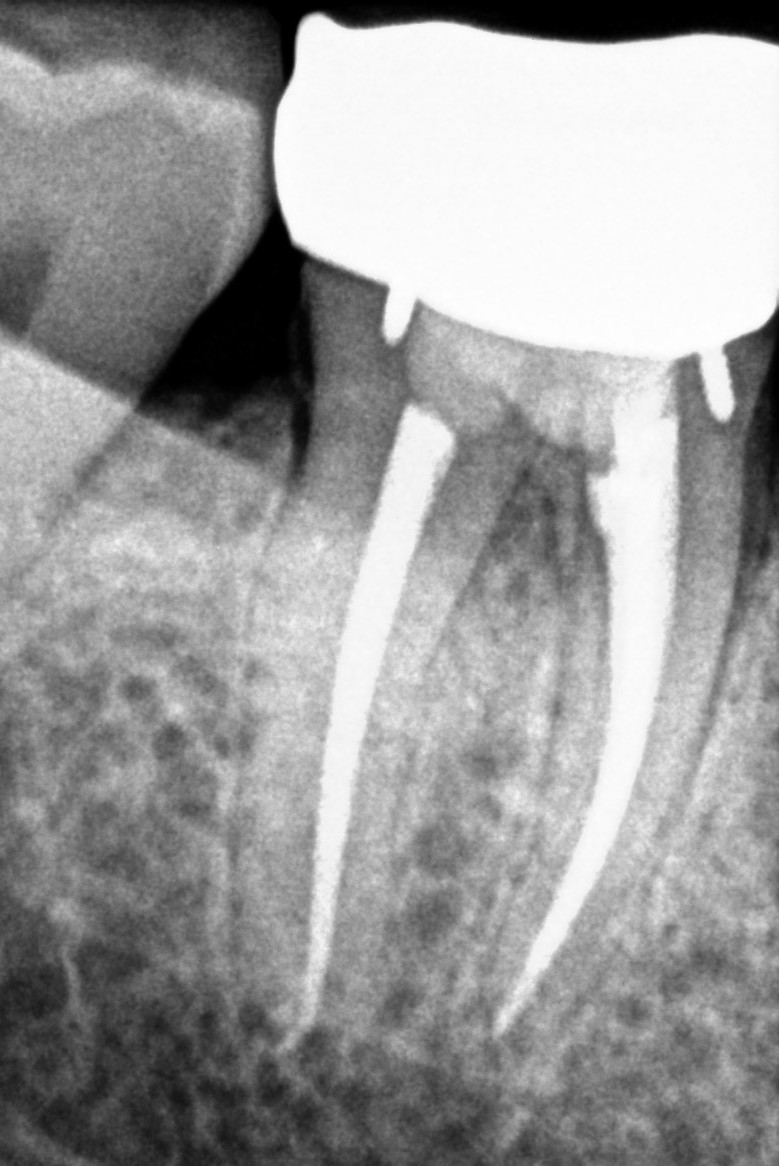

See My Work

Cases